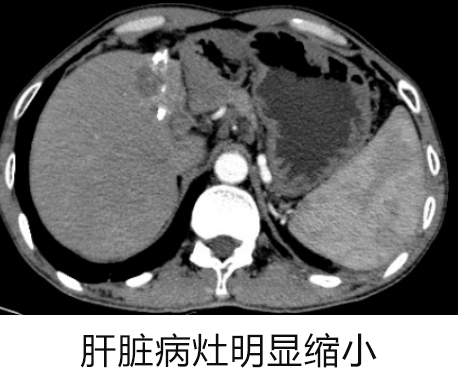

经过 3 个月的治疗后:

复查 CT 显示 肝脏左叶原发性肝癌介入栓塞术后病灶范围明显减小,伴肝内转移灶也有减少。患者继续口服索拉非尼+PD1 进行维持治疗。